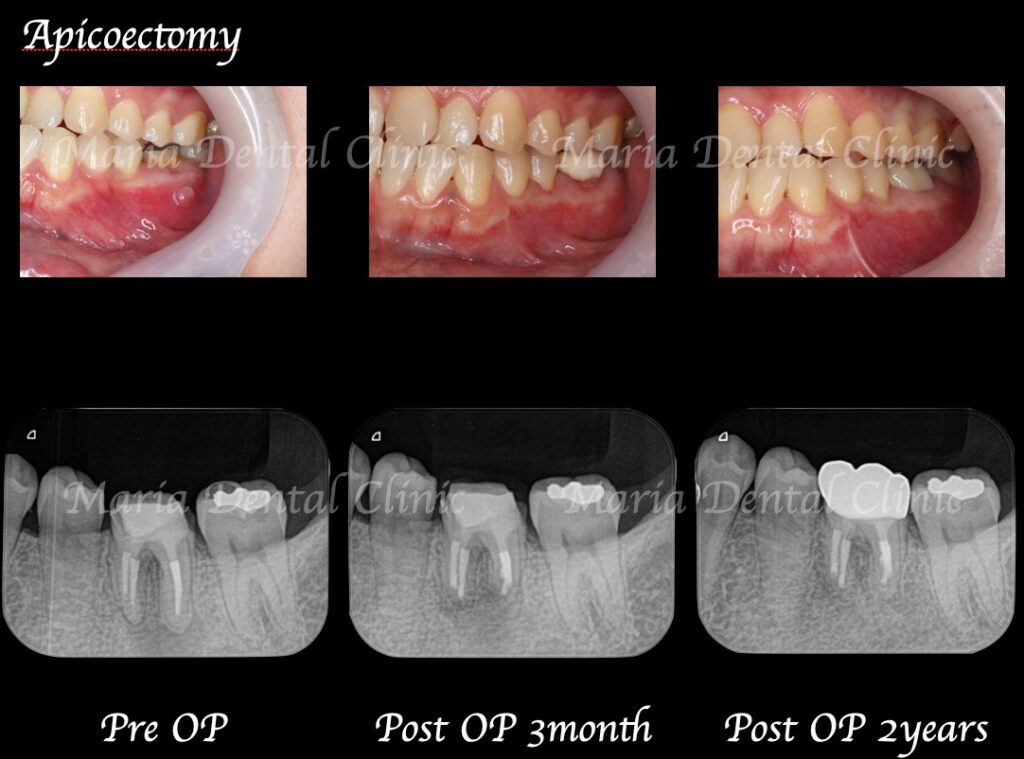

2年以上他院にて根管治療で通院されていた患者様の症例です。長期間通院したにもかかわらず症状は改善されず抜歯の宣告をされ、当院を受診されました。

左下6番直下は大きく腫脹し、サイナストラクト(瘻孔・フィステル)と言われる排膿路が確認できました。

当院にて再根管治療を施すもサイナストラクト(瘻孔・フィステル)の消失は確認できず、予後不良と判断し歯根端切除術を行った。

歯根端切除術を施した後にはサイナストラクト(瘻孔・フィステル)の消失が確認でき、根尖性歯周炎は寛解へ向かっていると考えられます。

今後、最終補綴処置を行い最低2年のフォローアップ(経過観察)を行い、レントゲンで注意深く根尖周囲組織の治癒を確認していきます。

2年間術後1年おきに経過観察を行った結果、歯根端切除術後に違和感や腫れはなく良好な治癒を確認しております。